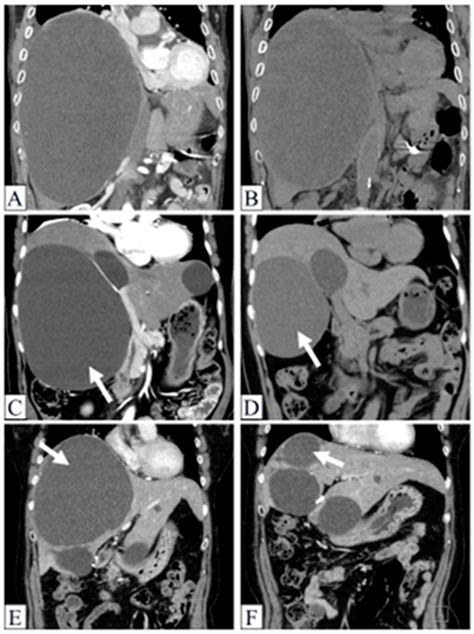

Because symptoms can overlap with other conditions like gallstones or gastric issues, diagnostic imaging is the gold standard for confirming that a patient is suffering from Symptomatic Liver Cysts. Doctors typically rely on:

CT Scan Provides detailed cross-sectional views to determine cyst size and location.